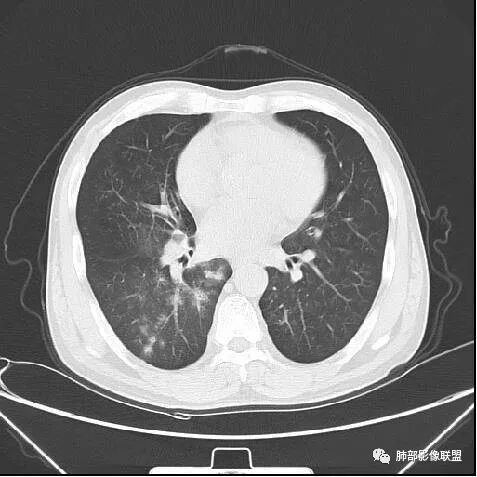

南边:紧贴着斜裂过来的一个病灶,它的特点是:外围大,内带小。它整个下叶背段体积与对侧相比稍微缩小一点,但是缩小地不是很厉害。外支朝前下走了,仔细看血管,肺动脉走行自然,直达远端。远端实变区是肉芽肿成分,稍微有一点低密度,没有明显坏死,稍微有一点点坏死。而且附近有很多卫星灶,附近很多斑片影,有一些明显有气道壁增厚,细支气管炎的特点,还有就是下叶其他段很多斑片状影。换个角度,第一如果是肺癌,刚才看到PET-CT提示肺癌伴阻塞性肺炎,这个是不符合的。第二如果是肺癌阻塞性肺炎,近端血管肺动脉走行不会那么自然集聚的,这个是不符合的。理由是:如果这个病灶是肺癌,那么明显属于中央型肺癌,中央型肺癌的特点是近端大,远端小,近端是一个肿块,远端阻塞,远端阻塞是阻塞性炎症或者不张,它应该体积缩小,斑片状实变,不会这么密实。刚才有老师提到支气管,这个片有缺陷的地方,给的图像好像那层,如果把其他图像拿开再重叠一下。

鉴别诊断:肺炎性肺癌,胸膜下起源,外围大,局部占位效应,有膨隆有收缩,这个不太支持。支气管走行里面没有看到支气管进入很自然堵塞的粘液栓的特点。附近这些磨玻璃影,它的磨玻璃影要么边界清楚,要么由内朝外蔓延的,而不是沿着支气管束蔓延的。而且附近斑片状影,有些似乎有结节感,但是大部分不是,它不是我们常见的磨玻璃样结节,有些有,导致像腺泡样结节那种椭圆的沿着血管束分布的,我会把肺炎型肺癌放在待排。

右肺下叶背断肿块,外围大,内带相对狭长         远端有膨隆,边缘模糊、凹凸不平         血管走形自然,病灶近端支气管通畅,沿支气管树蔓延         周边有多发病灶,多为磨玻璃密度且边界不清。